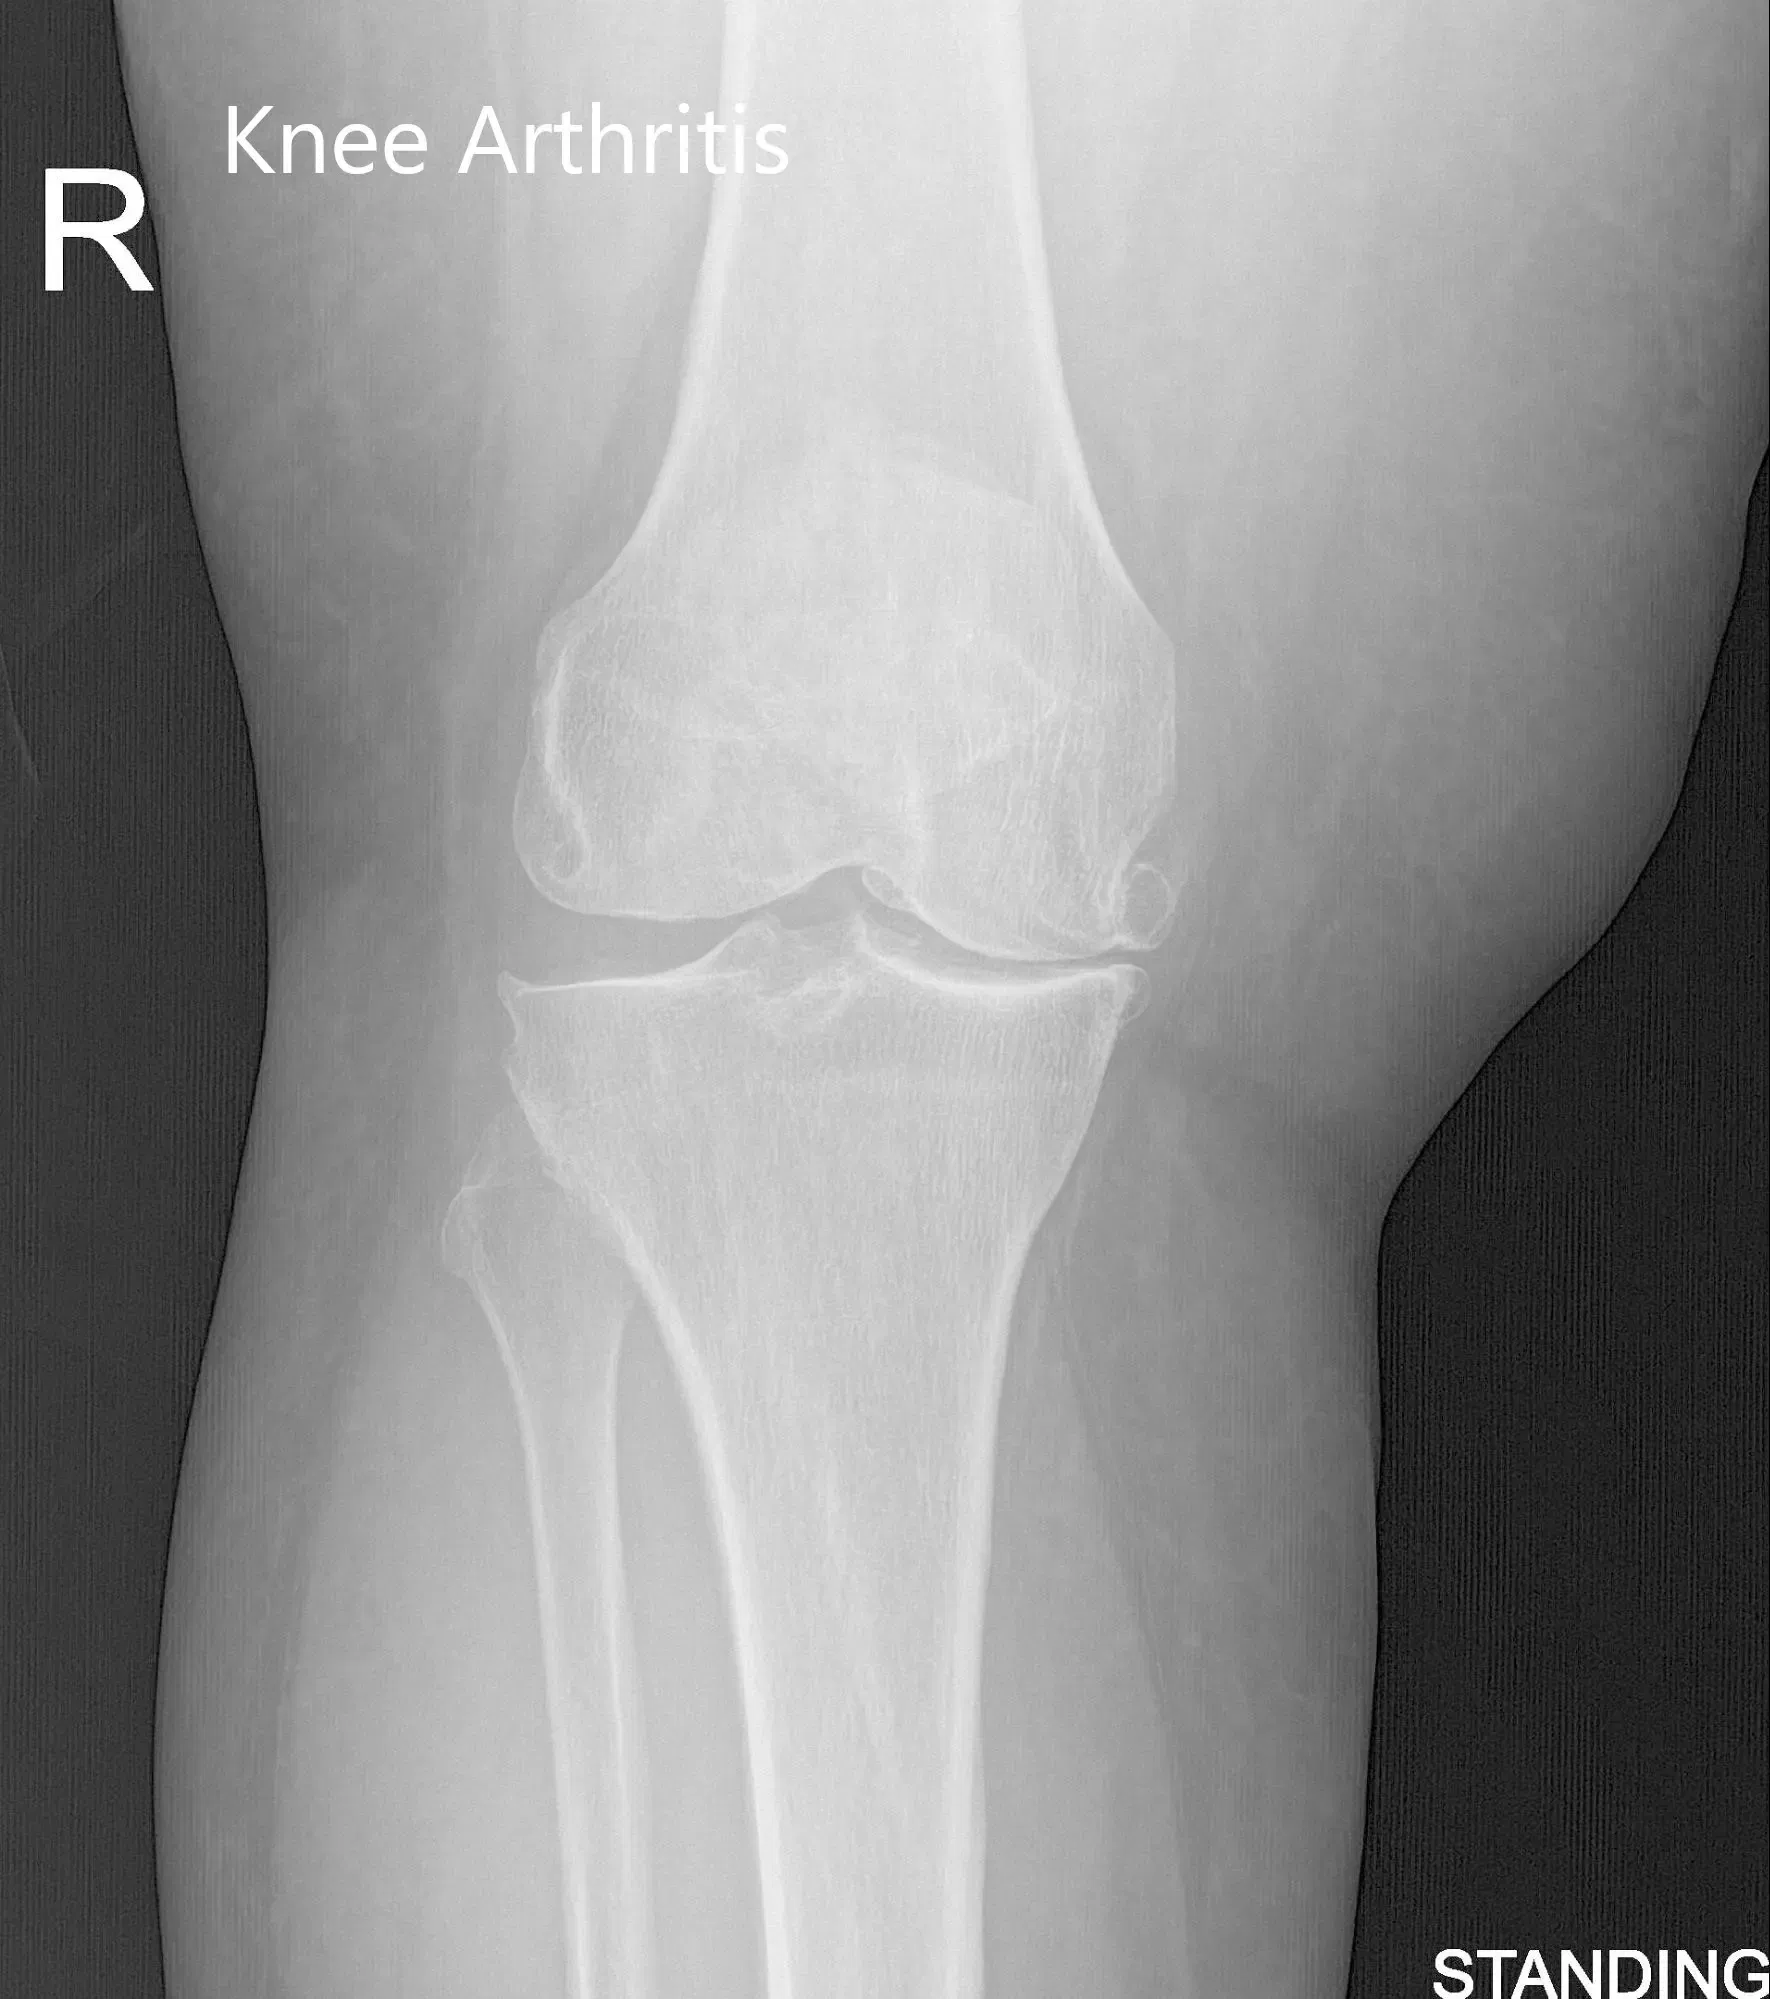

Physical examination revealed genu varus deformity and mildly swollen right knee joint. There was marked joint crepitus throughout the range of motion with moderate medial and lateral joint line tenderness and patellar facet tenderness. Imaging studies revealed marked narrowing of the medial joint compartment and patellofemoral joint compartment with moderate osteophyte formation.

Pre-Operative AP and Lateral X-Ray views of the right knee (standing)